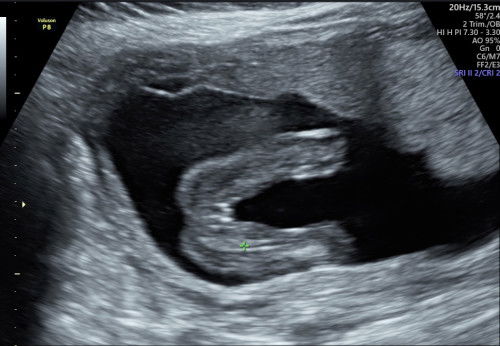

girl or boy

Hi mommies. ni scan saya masa week 18. takda niat nk tengok gender lagi tapi dr scan kata mcm girl. nk tanya pendapat mommy2, kalau mcm ni girl ke atau ada possibility lain nk jadi boy? 🤣 kita ni dah exsited kalau girl hihi. nk scan lagi mcm nk tunggu 2-3 minggu lagi. tapi curious sgttt. #firstmom